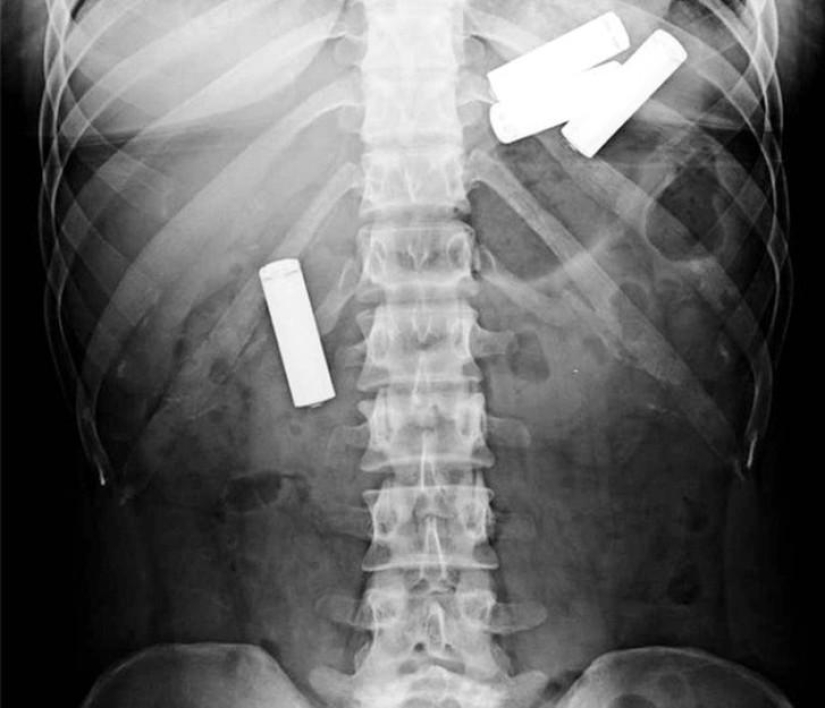

13. And here are the batteries!